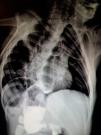

Paciente masculino de 9 años de edad en quien se diagnosticó fístula traqueoesofágica y atresia esofágica al nacer; las mismas que fueron reparadas quirúrgicamente. En cita de seguimiento con los servicios de Pediatría y Gastroenterología de nuestro centro, se le realizó la presente radiografía de tórax y abdomen, la cual muestra presencia de situs inversus y anomalías de la morfología y la fusión vertebral, así como los cambios posquirúrgicos de la reparación esofágica, con lo cual se integran los hallazgos característicos de la asociación VACTERL (fig. 1).